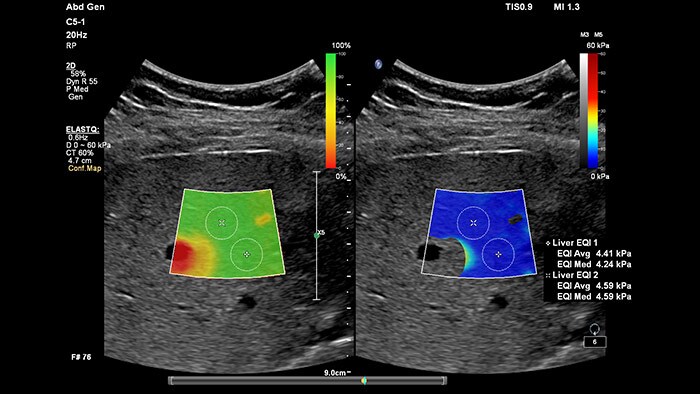

La elastografía por ultrasonidos de onda transversal ofrece un método no invasivo, reproducible y fácil de poner en práctica para evaluar la rigidez tisular. Los estudios realizados apuntan a que, en lugar de un costoso y doloroso procedimiento de biopsia, una sencilla exploración por ultrasonidos con elastografía de onda transversal podría convertirse en el procedimiento habitual para evaluar el estado de las enfermedades hepáticas. La elastografía por onda transversal de alto rendimiento de las imágenes con ElastQ incluye la evaluación cuantitativa de la rigidez tisular, codificada con colores, en extensas regiones de interés (ROI) en tiempo real. Las imágenes con ElastQ también ofrecen la posibilidad de efectuar mediciones retrospectivas en imágenes almacenadas; además, una exclusiva pantalla con un mapa de confianza emplea el análisis inteligente para ofrecer la garantía adicional de que las mediciones del usuario se han obtenido en zonas tisulares con una propagación adecuada de ondas transversales.

La medición de la rigidez hepática se obtiene en cuestión de segundos por medio de una sencilla exploración no invasiva.